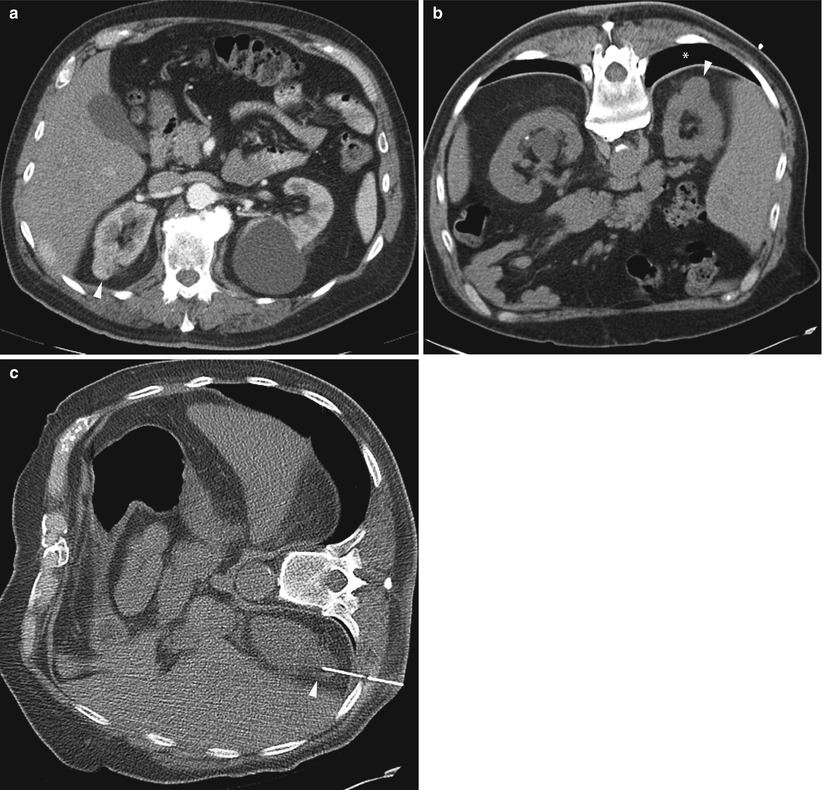

From www.researchgate.net

CTguided biopsy of the lesion Download Scientific Diagram Pain After Ct Guided Biopsy Normal activity can typically be resumed the day following the procedure. To keep you free of pain during the procedure, you may be given anesthesia or sedating medicines. Needle biopsy carries a small risk of bleeding and infection at the site where the needle was inserted. It typically takes several days. Pain resulting from the procedure usually resolves within a. Pain After Ct Guided Biopsy.